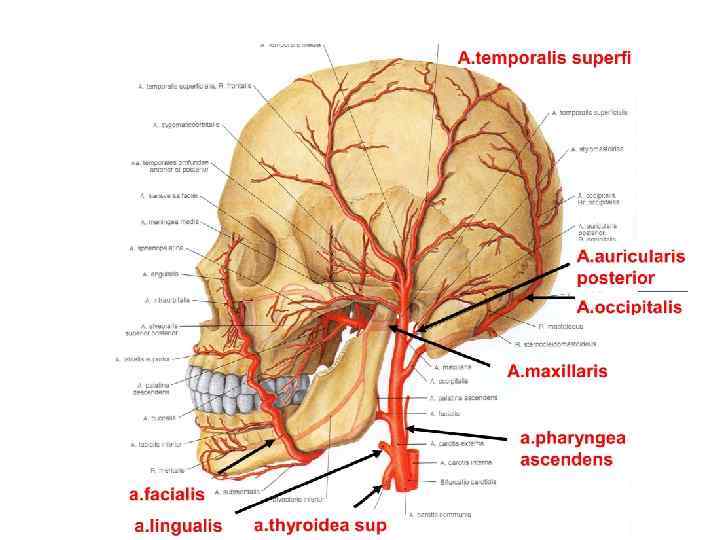

Анатомия: Задняя соединительная артерия мозга

Раздел: Фотоэссе